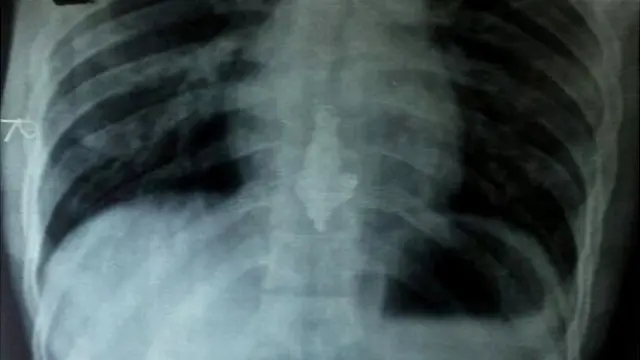

मुंबई में सायन अस्पताल ने अनिल के पेट के एक्स-रे में नेकलेस देखने का बाद उसे चार बार एनीमा भी दिया था.

अधिकारियों के अनुसार नेकलेस निकलने मे अधिक वक्त लगा क्योंकि इसका बड़ा पेन्डेन्ट इसके निकलने में बाधक बन रहा था.